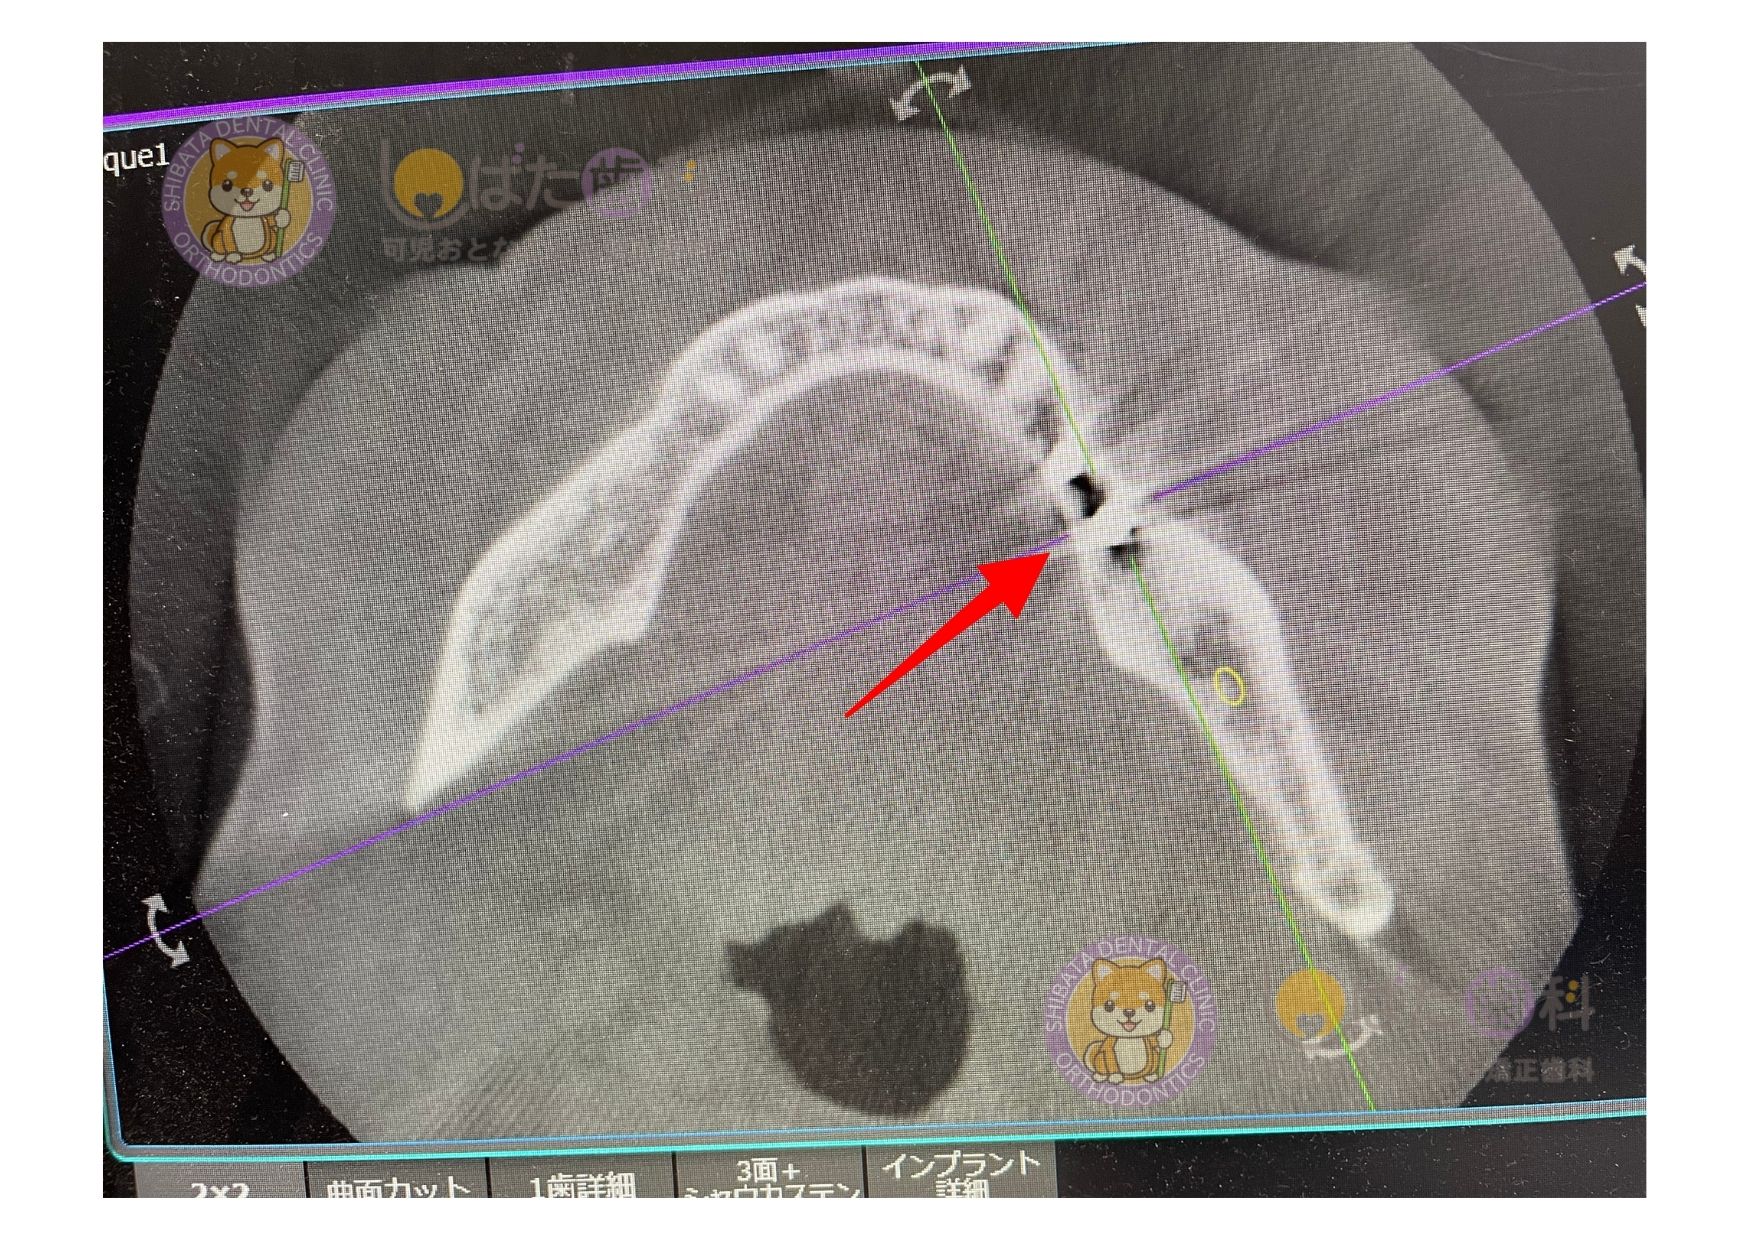

これは当院での実例です。上写真はとある患者さんの初診時CT画像です。インプラントを希望されており他院では骨がないと(矢印部)断られてしまい、当院でも治療が難しいのかセカンドオピニオンで相談に来た患者さん。

パッと見て分かる通り、反対の骨の幅を比べると極端に骨の量が少ないことが分かります。

協同ドクターとも意見を重ねた結果、GBR法(骨を増やす治療)を行い3〜6ヶ月骨待ちをした上で、径の一番小さいインプラントなら治療可能というという診断になりました。

結果、下写真(インプラント治療終了後CT画像)のように無事にインプラントを埋入ことができました。

予後も良好で問題なく使えています。